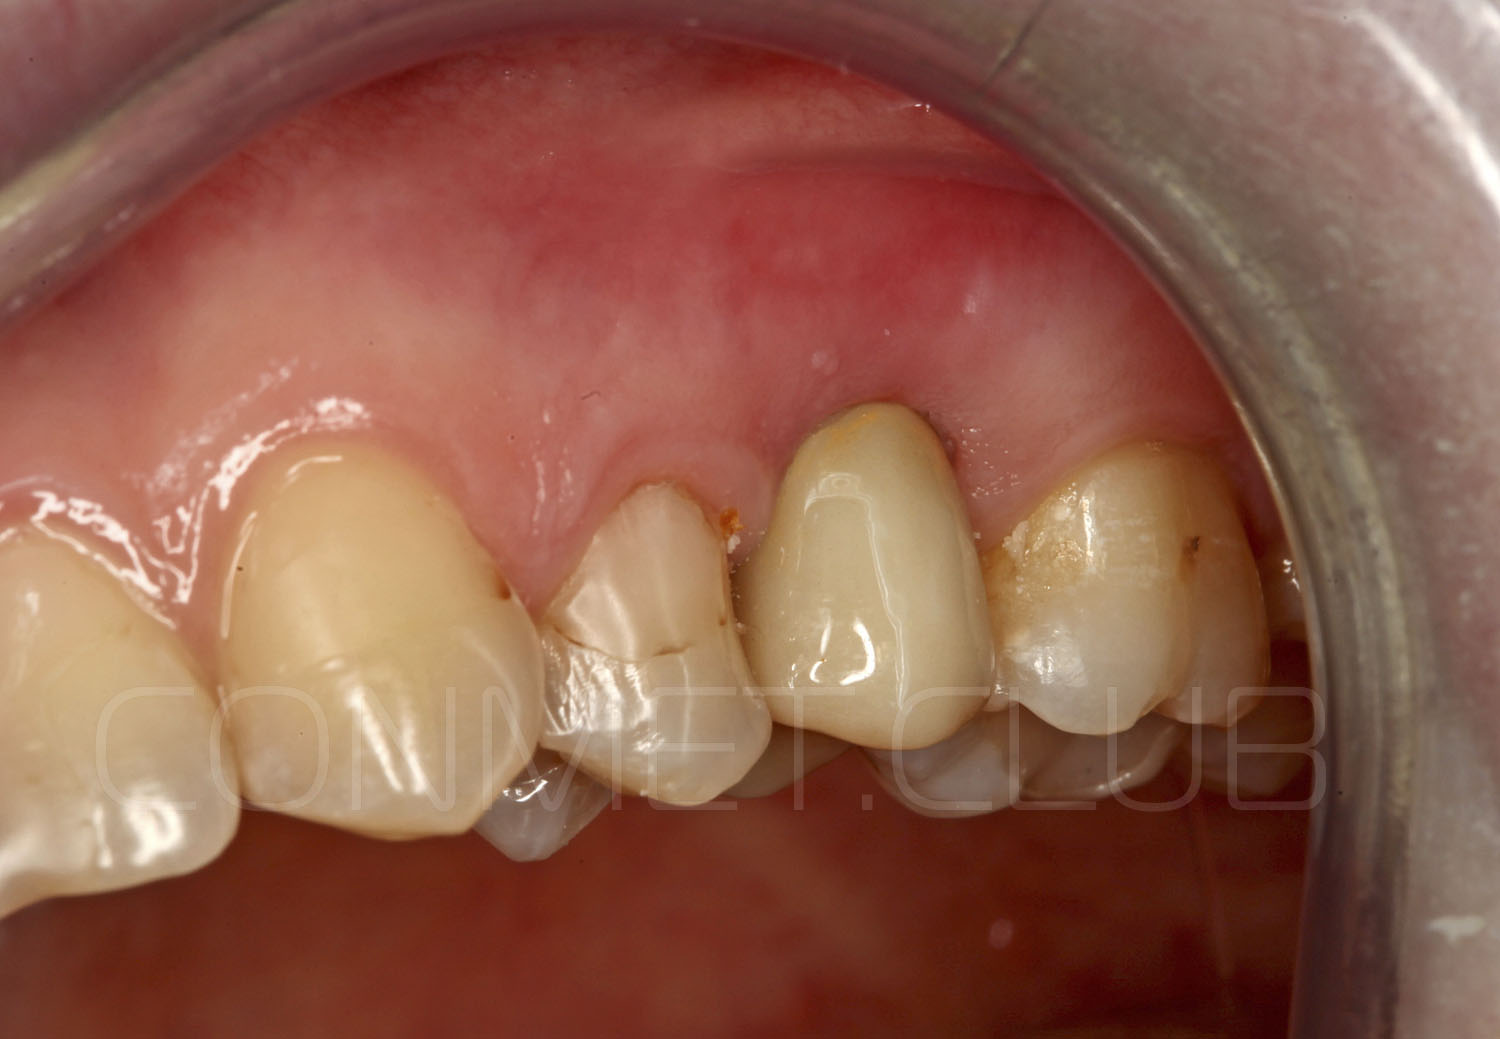

Вид в полости рта пациента перед операцией. С момента удаления зуба 25 прошло 4 месяца. Планируется проведение операции без откидывания слизисто-надкостничного лоскута.